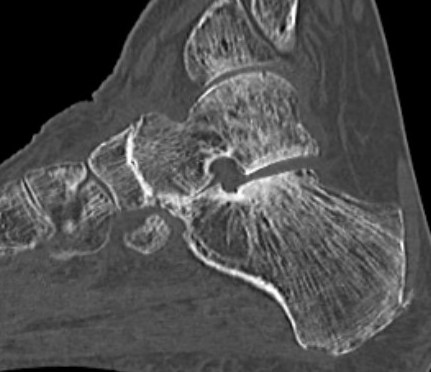

Subluxation of TNJ with advanced STJ OA

TNJ OA with posterior / medial / anterior facet OA of the subtalar joint